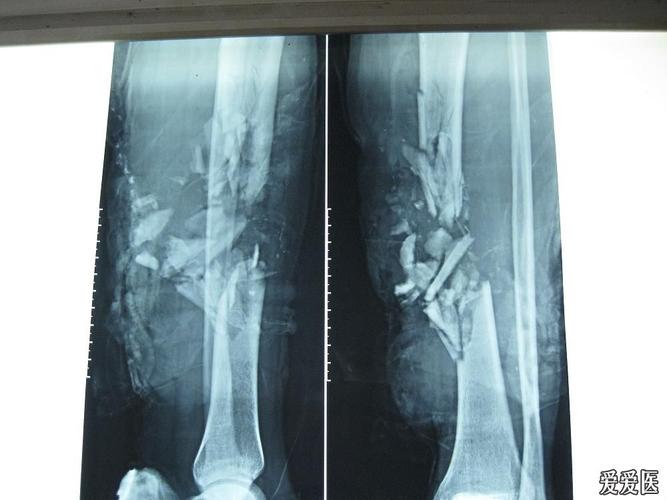

腿粉碎性骨折,跟骨粉碎性骨折

男45岁,胫骨远端粉碎性骨折

请教胫骨开放性粉碎性骨折的治疗

微创手术治疗胫骨干粉碎性骨折

胫腓骨粉碎性骨折,小切口植入加长钢板,告别传统大切口

胫腓骨粉碎性骨折并伴有腓总神经损伤,胫骨用髓内钉固定,腓骨用钢板

小腿粉碎性骨折图片

粉碎性骨折图片

粉碎性骨折x光

粉碎性骨折片子图片

粉碎性骨折x光片